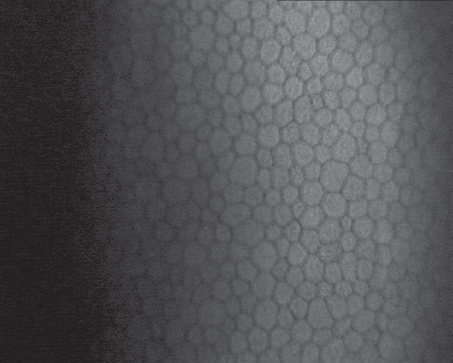

Fig. 3. Confocal microscopy, endothelial cells before YAG-laser activation of trabecular meshwork

Рис. 3. Конфокальная микроскопия, эндотелиальные клетки до YAG-лазерной активации трабекулы